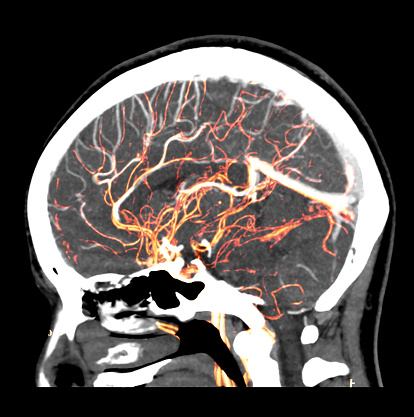

Coronary artery disease or other heart conditions like valve defects, irregular heartbeat or atrial fibrillation can all affect your risk for stroke for differing reasons. The plaque that builds up in your arteries from coronary artery disease can block the flow of oxygen to the brain, while irregular heartbeat conditions and valve defects can cause blood clots, which could break loose and cause a stroke.